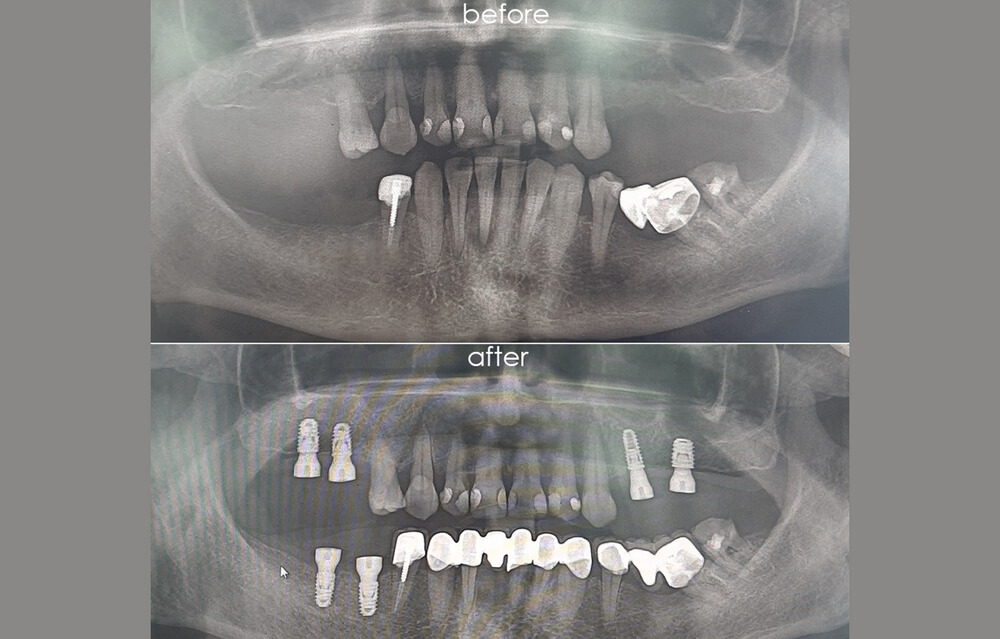

İmplant cerrahisi sanılanın aksine çoğu kez ağrısız ve kısa süreli bir operasyondur. Genellikle cerrahi operasyondan sonraki 3. ve 4. ayda hastalar dişlerine kavuşur.